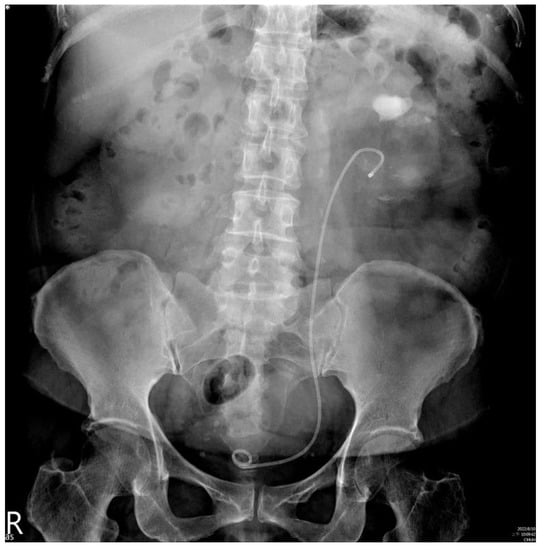

Percutaneous Nephrolithotomy Combined Antegrade Flexible Ureteroscope for Complete Staghorn Stones: A Case Report of a New Concept of Stone Surgery

2. Case Presentation